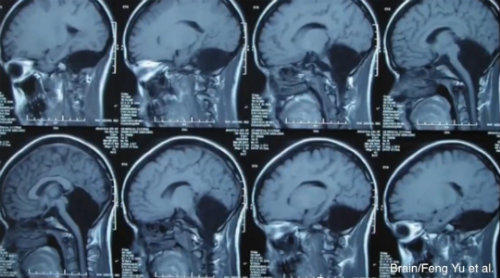

Doctorii au descoperit ca o femeie de 24 de ani a trait pana acum fara cerebel. Cazul evidentiaza plasticitatea remarcabila a creierului DoctorH Actualitate SEPT. '14 Doctorii au descoperit ca o femeie de 24 de ani a trait pana acum fara cerebel. Cazul evidentiaza plasticitatea remarcabila a creierului